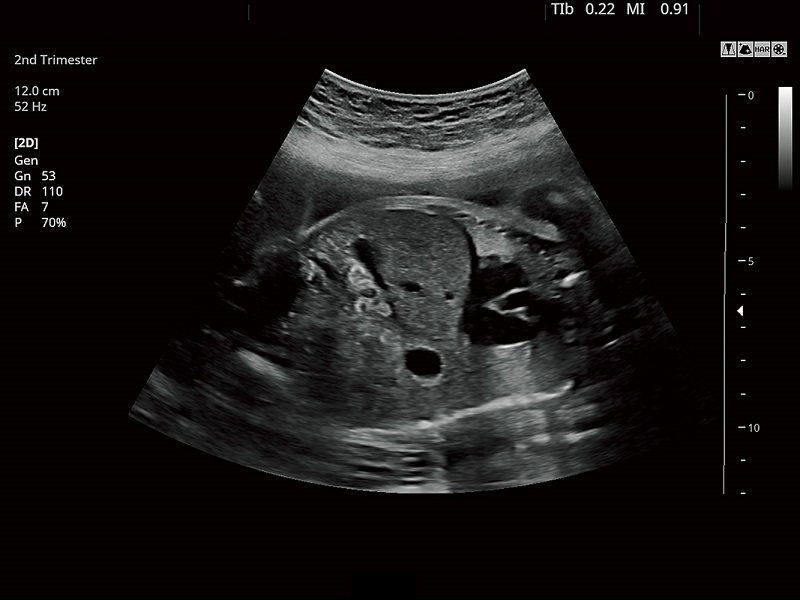

FUJIFILM FUTUS – Ultrasound System

FUTUS features great imaging technologies to support a clear view and confident diagnoses.